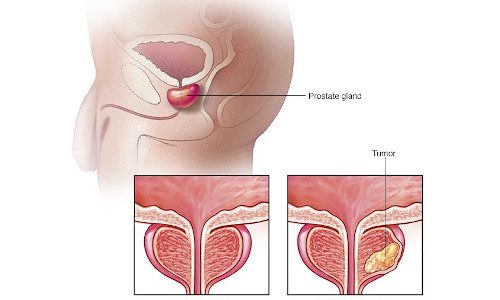

- ონკოლოგია

ტეგი: სხივური თერაპია